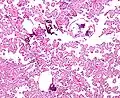

Micrograph of a choroid plexus papilloma. H&E stain.

Micrograph of a choroid plexus papilloma. H&E stain. Plexuspapillom Detail